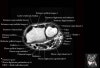

- Axial section

Axial T1 evaluates the tendons of the wrist and carpal tunnel, including the flexor retinaculum.

Axial PD fat suppressed evaluates the tendons of the wrist and carpal tunnel, including the median nerve.